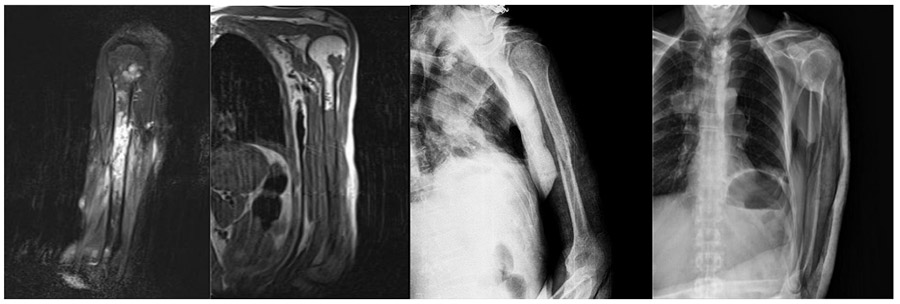

CASE 6: Lung cancer metastasis to the left arm bone (humerus) leading to a fracture.

Before the surgery: X-ray shows a displaced fracture in the middle of the left humerus, and MRI shows a metastatic focus filling the middle portion of the humerus and also involving the upper portion.